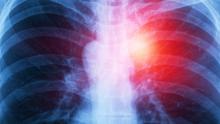

Malignant pleural mesothelioma is an aggressive tumor of the pleura. Extended pleurectomy and decortication is a lung sparing cytoreductive procedure used in the management of this disease for curative intent.

This video shows the case of a forty-eight-year-old woman with occupational exposure to asbestos. She had a right VATS pleural biopsy, which confirmed diagnosis of epithelioid malignant pleural mesothelioma. She was also being investigated for a concurrent breast lump. A core biopsy also confirmed invasive ductal carcinoma of the breast. The patient’s other comorbidities included Barret’s esophagus, endometriosis, and a hiatal hernia.